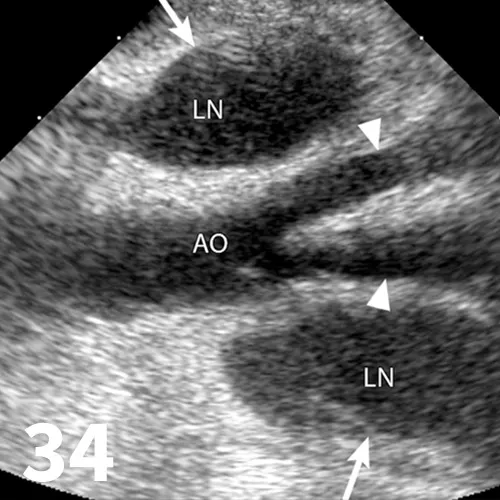

Survey radiography can be used to evaluate the size, shape, and opacity of the prostate gland (Figures 31 and 32). Ultrasonography has the advantage of providing tissue-architecture information. Prostatic abscesses, internal cysts, and paraprostatic cysts are readily visualized on ultrasonography. Ultrasonography can also aid in diagnosing benign hyperplasia (homogenous echotexture with intact capsule) and prostatic neoplasia (heterogenous with course echotexture and irregular margins) (Figure 33) and with identifying any potential source of excess androgen production (eg, adrenal glands, retained testes) in cases of suspected squamous metaplasia of the prostate gland. Mineralization of the prostate in a neutered dog is suggestive of neoplasia and can be detected by both survey radiography and ultrasonography. Sublumbar lymph nodes can also be evaluated by ultrasonography, whereas radiography is best for evaluating the adjacent lumbar spine (Figures 34 and 35).

Figure 31.

The prostate gland (arrows) in this intact male dog is enlarged but normal in shape with smooth margins and soft tissue opacity. Although this is consistent with benign prostatic hypertrophy, ultrasound would be useful to further define tissue architecture.